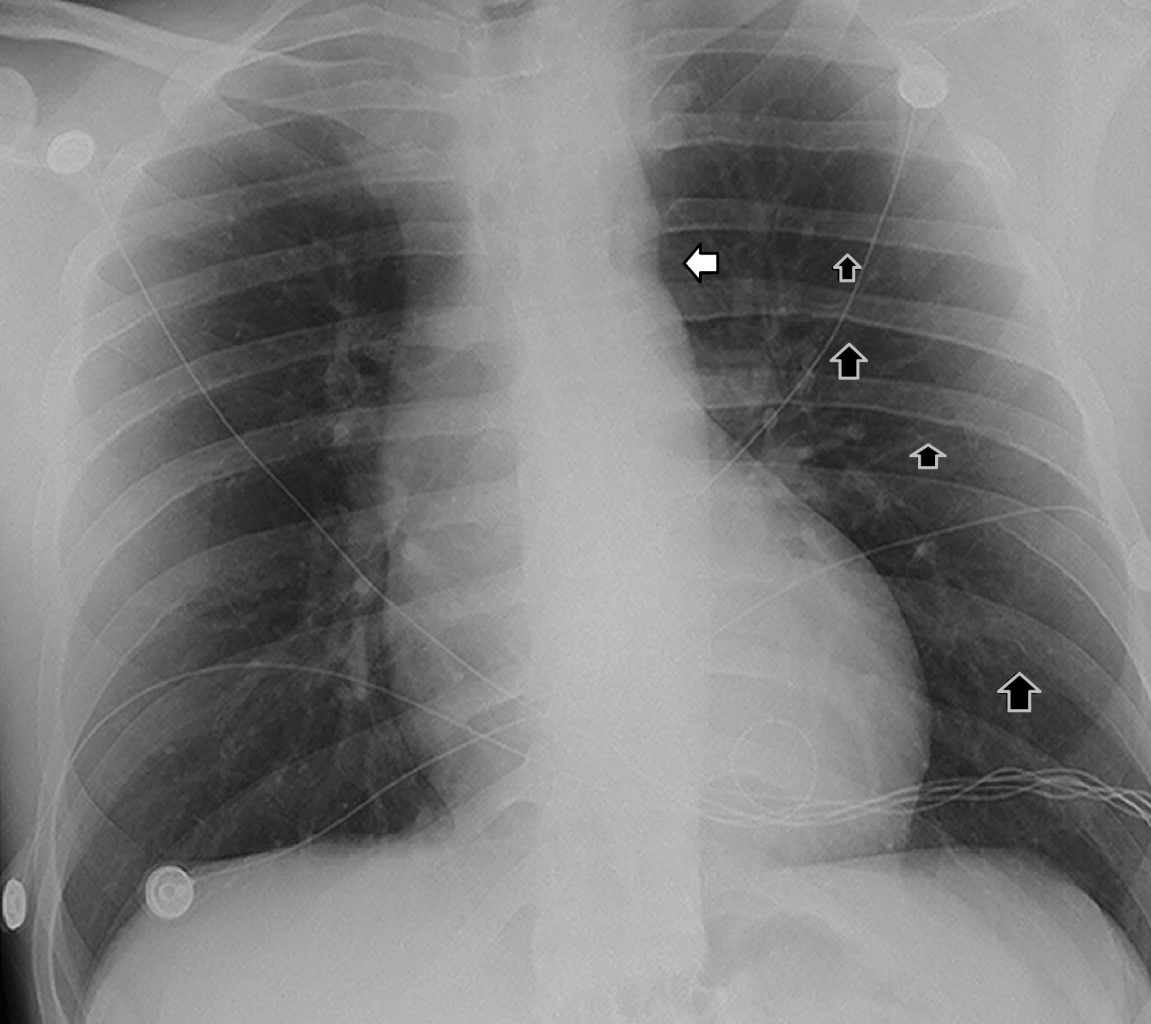

Coartación aórtica asociada a válvula aórtica bicúspide complicada con aneurisma aórtico postdisección

Sánchez-Amaya DJ, Godínez-Córdova LB, López-Lizárraga MÁ, Araiza-Garaygordobil D, Arias-Mendoza A

coartación aórtica, disección aórtica crónica, aneurisma aorta ascendente, válvula aórtica bicúspide.

La coartación aórtica es un trastorno congénito que afecta no solamente a la aorta, sino que también puede asociarse a válvula aórtica bicúspide y predispone a síndromes aórticos. Se reporta el caso de un paciente de 28 años de edad con hipertensión secundaria debido a coartación aórtica postductal asociada a válvula aórtica bicúspide que a su vez presentó disección crónica de la aorta ascendente. La coexistencia de enfermedad valvular aórtica, así como múltiples condiciones aórticas, es una situación rara que requiere una evaluación altamente especializada para garantizar un resultado favorable. El tratamiento se estableció en dos fases: aortoplastia con colocación de stent y luego cirugía de reemplazo aórtico y valvular, con una recuperación favorable.

Figura 1